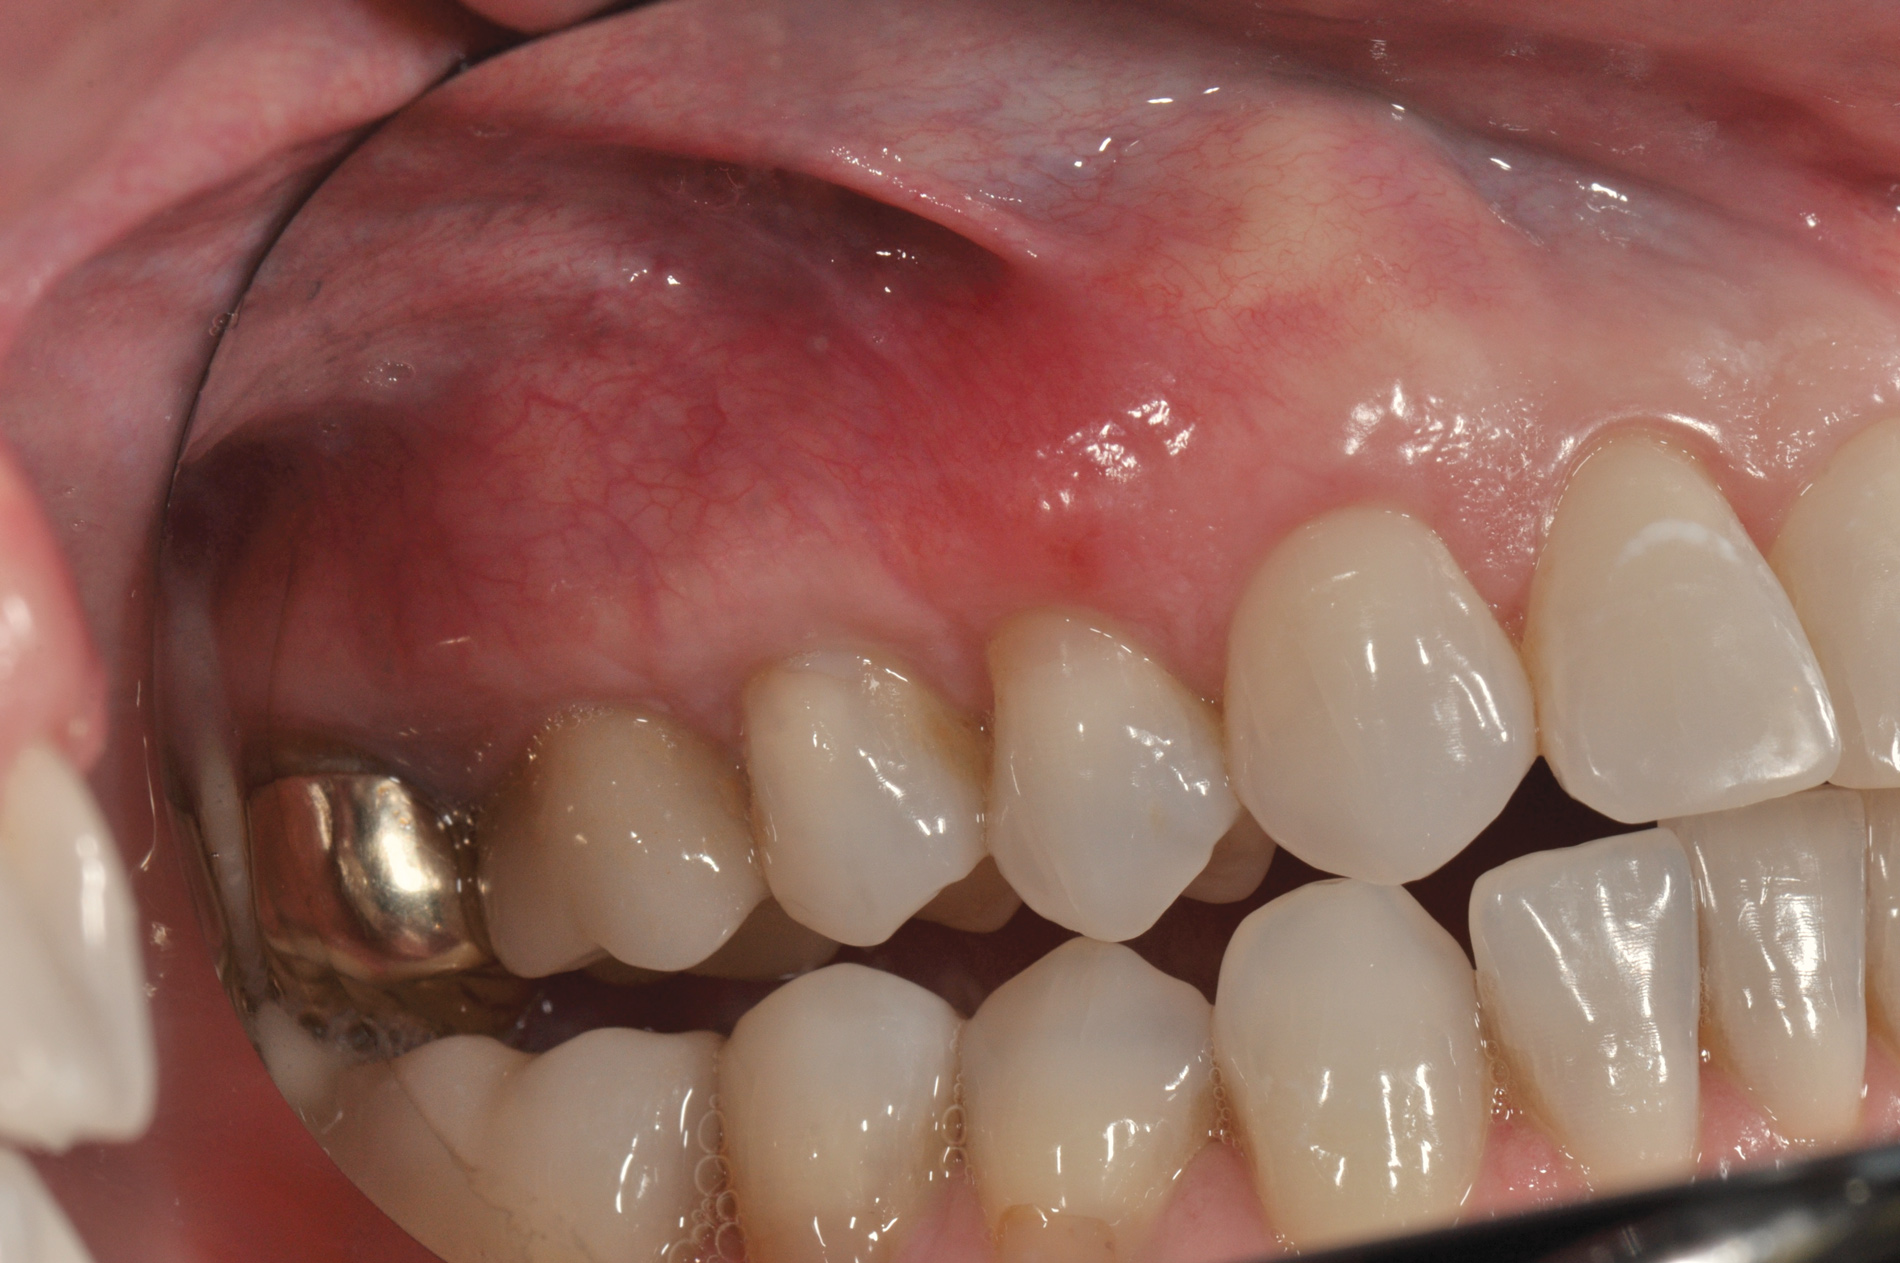

(25.) Preoperative view.

Figure 25